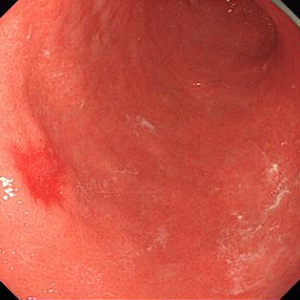

《胃ESDの実際》

食道表在癌、早期胃癌の治療法として当科では積極的にESDを行っています。ESDとは内視鏡的に使用可能な高周波メスを使って、粘膜下層のレベルで病変を剥がし取る手技です。早期の小さな癌に対しては今までも内視鏡治療が行われてきましたが、ESDにより従来の内視鏡治療法(EMR)では切除困難であった大きな病変や、瘢痕を認める病変を一括切除できるようになりました。体を切開することなく組織も温存できるため、患者の身体的負担が少ない低侵襲医療のひとつです。

食道ESDは年間約15例、胃ESDは年間約40例ほど行っております。